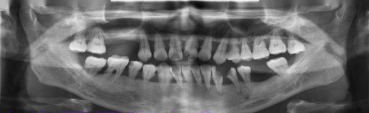

牙周炎患者X光片,全口牙齿出现2~3度的松动,无法咀嚼。